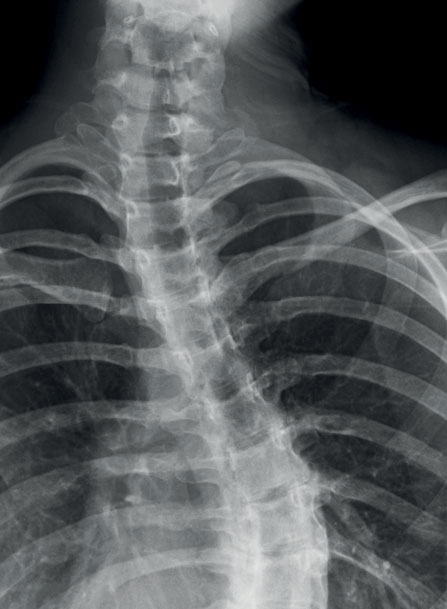

هي عبارة عن التهاب غير طبيعي في العمود الفقري. فصحيح ان لكل منا التواء في العمود الفقري بدرجة معينة، لكن في هذه الحالة يكون الالتواء لدى من يعاني الScoliosis أكثر حدةً وبشكل مفرط، فقد يبدو العمود الفقري بشكلC أو بشكل S.

يسبب التواء العمود الفقري حدبة في الظهر تلفت الانتباه ويمكن ملاحظتها مباشرةً. كما يمكن أن يلاحظها أي طبيب لدى انحناء الشخص. ويلاحظ أن أحد الوركين يكون أعلى من الآخر.

أيضاً في الفحص العيادي يلاحظ أن جانبي الجسم غير متماثلين. هذه العوامل كلّها تدعو إلى إجراء صورة شعاعية تؤكد وجود التواء في العمود الفقري.